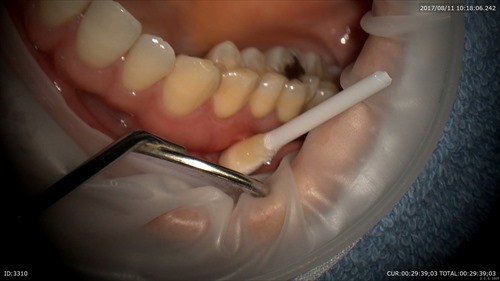

こんにちは。院長の武川です。今日は祝日ですが診療しています。本日はマイクロぺリオを行いました。歯周病の治療をマイクロスコープ下で行いました。

表面麻酔を塗って(海外製)無痛で出来るコツ!

歯石発見!!